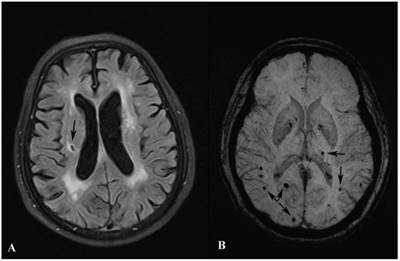

LOD patients were more likely to be female, lack of social support, with severe WML and cognitive dysfunction than control group. Besides, LOD patients had higher prevalence of SBIs and MBs, especially lesions in the left hemisphere, SBIs in basal ganglia and lobar MBs than control group. (All p<0.05). Details were listed in Table 1. Examples of SBIs and MBs were illustrated in Figure 1.

Figure 1

Images of SBI and MB. Image A shows a SBI (black arrow) in the right cerebral hemisphere. Image B shows MBs (black arrows) in both hemispheres.